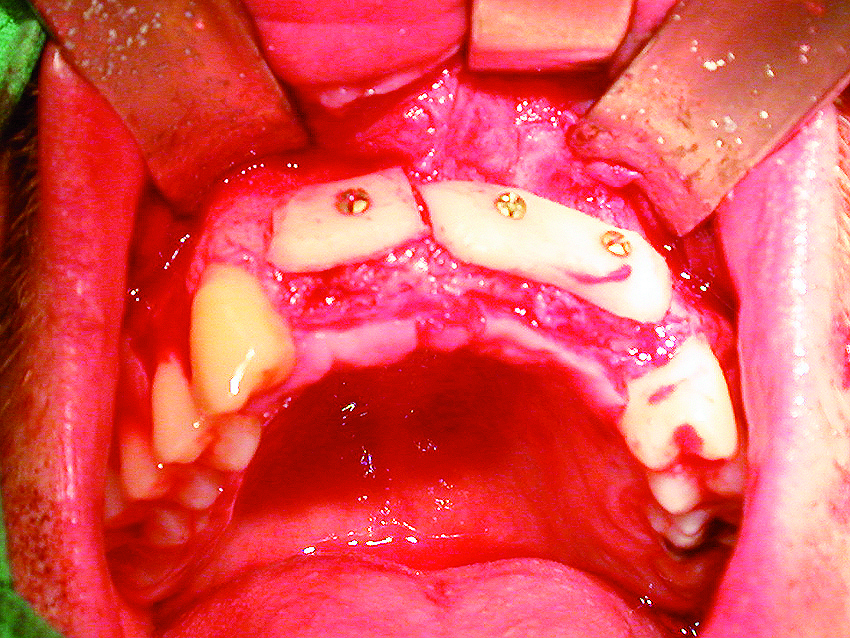

• transversal : dans ce cas, il correspond à la disparition de la table externe ( photos 1, 2 et 3 ) ;

Les traitements varient en fonction de l’importance et de la morphologie des défauts osseux : prélè

vements ramiques, symphysaires, greffes en onlays, ostéotomie de Summers, technique de fenêtre latérale (sinus lift), utilisation d’implants courts et de différents diamètres… Lors du sinus lift, les matériaux de comblement peuvent être